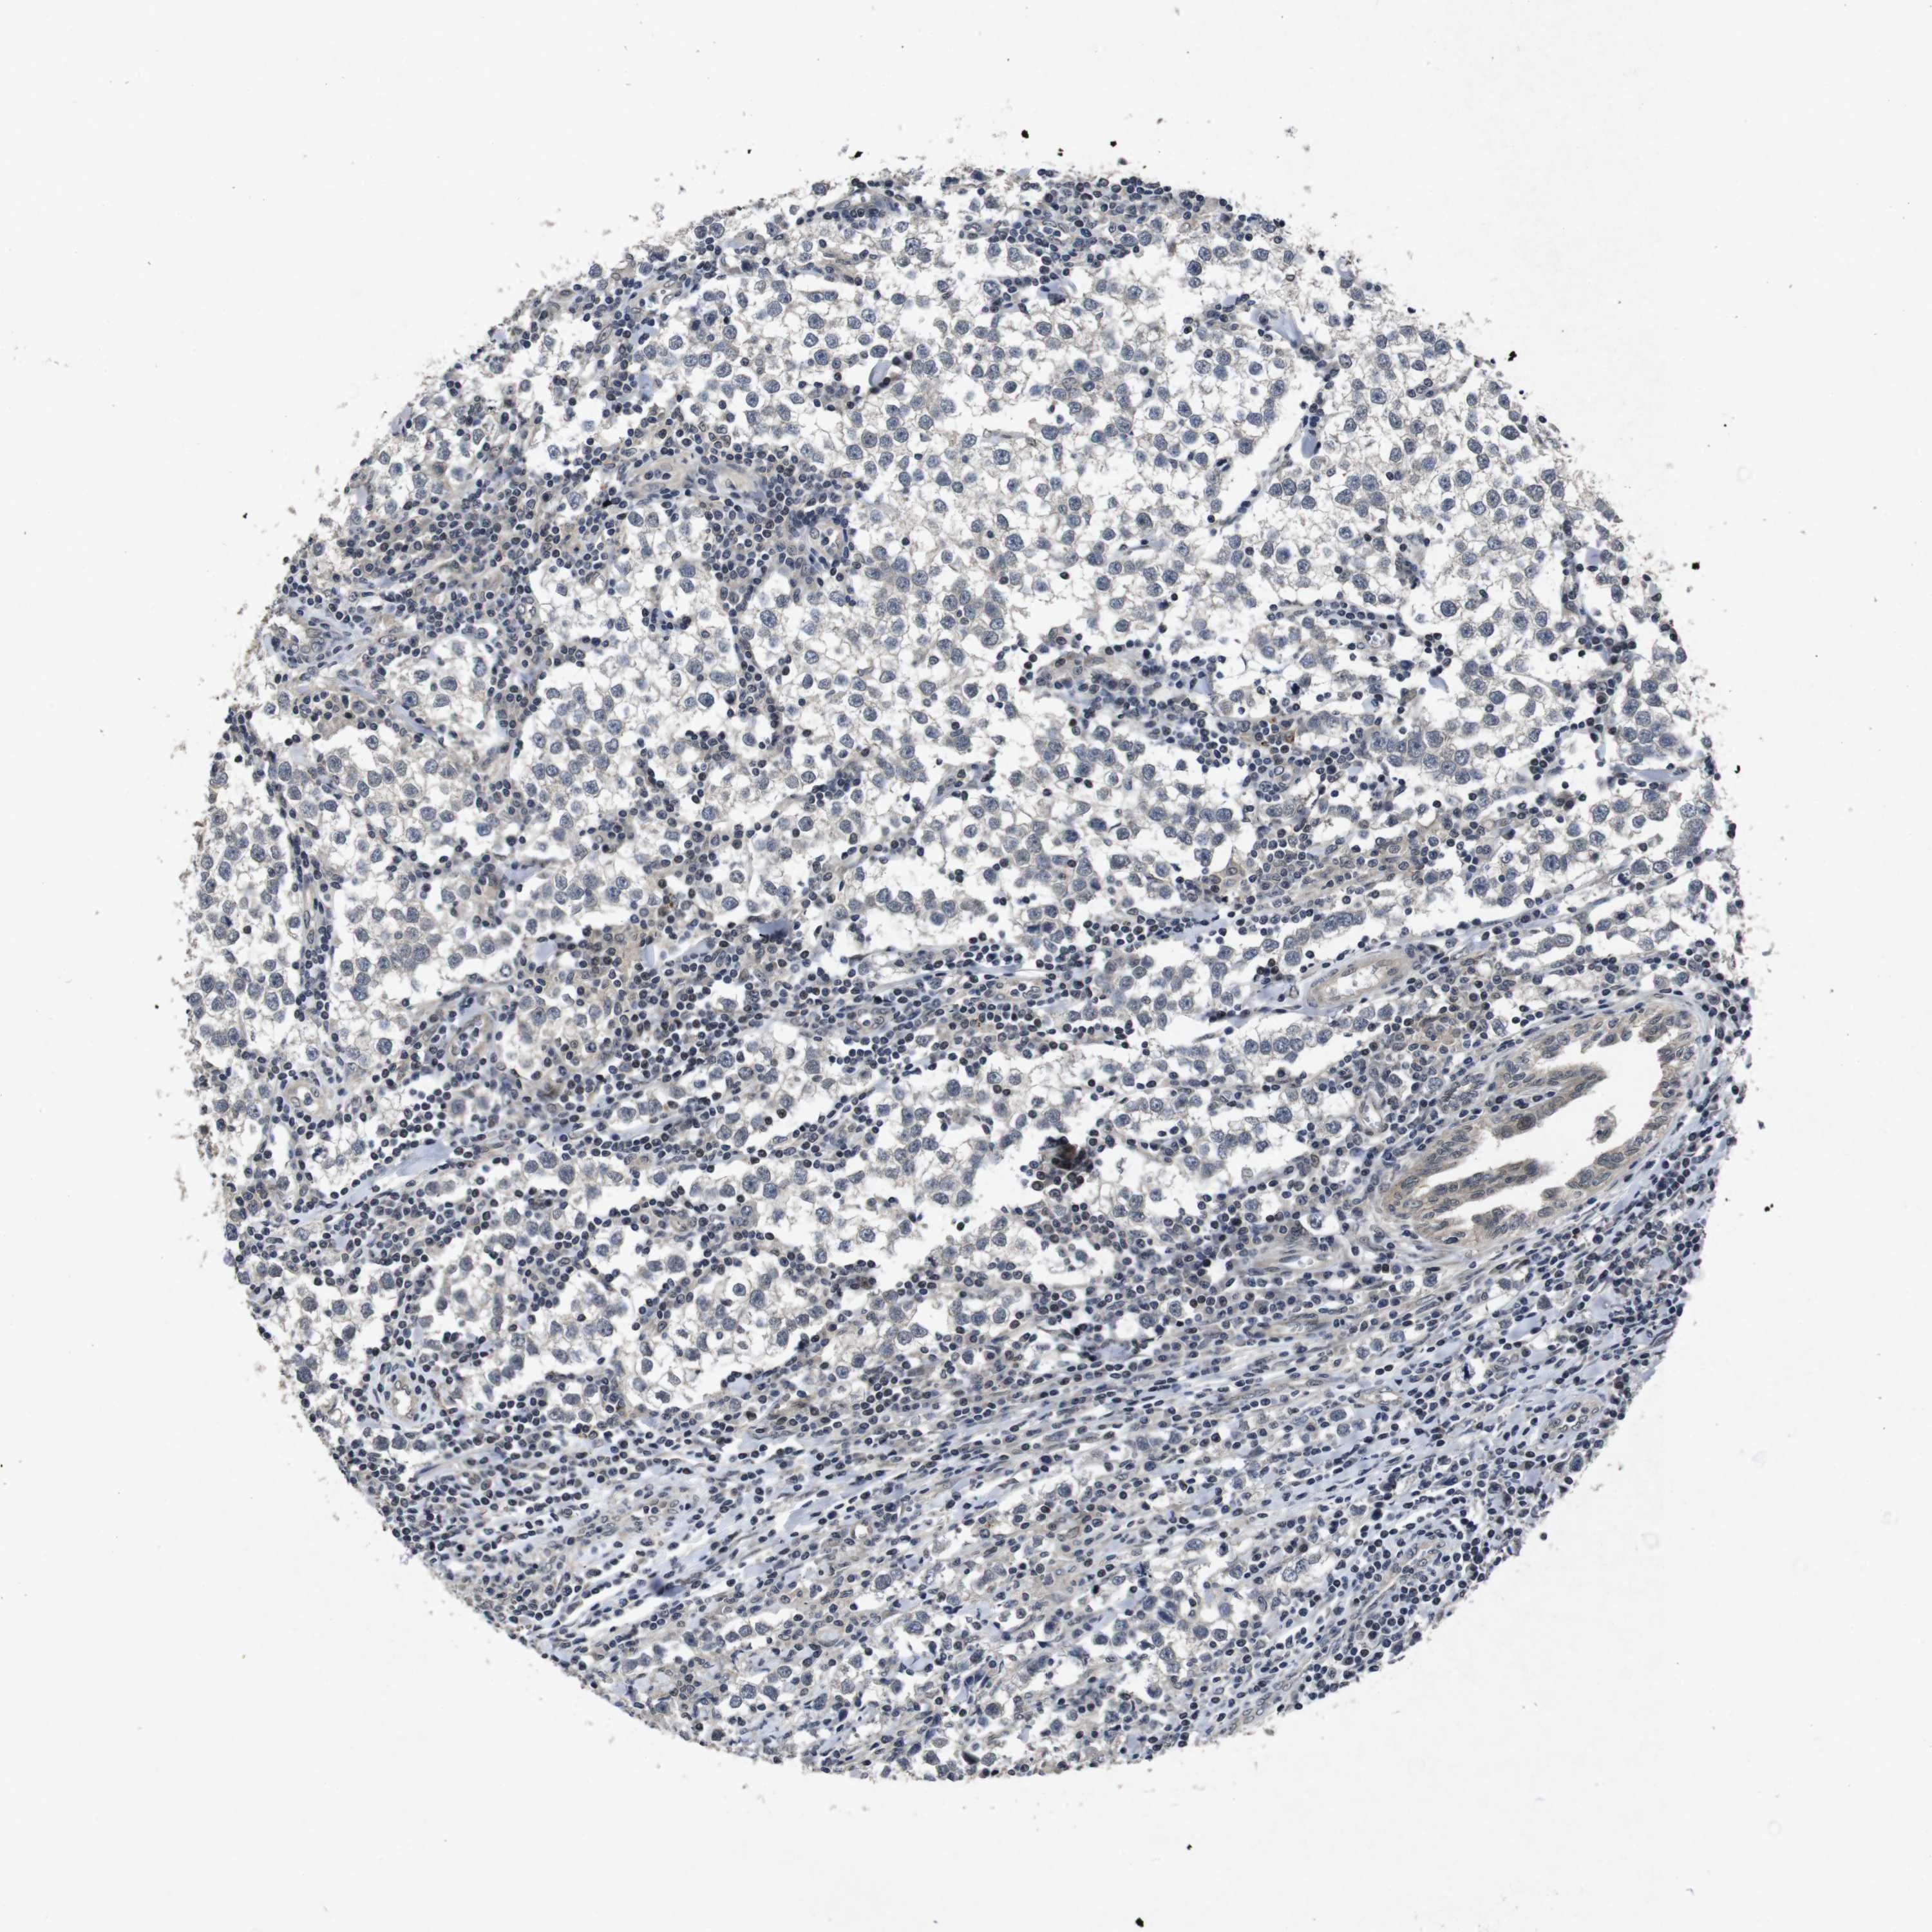

TESTIS CANCER - Protein expressioni

A mouse-over function shows sample information and annotation data. Click on an image to view it in a full screen mode. Samples can be filtered based on level of antibody staining by selecting one or several of the following categories: high, medium, low and not detected. The assay and annotation is described here.

Note that samples used for immunohistochemistry by the Human Protein Atlas do not correspond to samples in the TCGA dataset.

Antibody stainingi

Antibody staining in the annotated cell types in the current human tissue is reported as not detected, low, medium, or high, based on conventional immunohistochemistry profiling in selected tissues. This score is based on the combination of the staining intensity and fraction of stained cells.

Each image is clickable and will lead to virtual microscopy that enables deeper exploration of all samples and also displays staining intensity scores, fraction scores and subcellular localization as well as patient and tissue information for each sample.

Antibody HPA026441

Antibody CAB013090

Staining

High

Medium

Low

Not detected

Intensity

Strong

Moderate

Weak

Negative

Quantity

>75%

75%-25%

<25%

None

Location

Nuclear

Cytoplasmic/membranous

Cytoplasmic/membranous,nuclear

Carcinoma, Embryonal, NOS

Seminoma, NOS